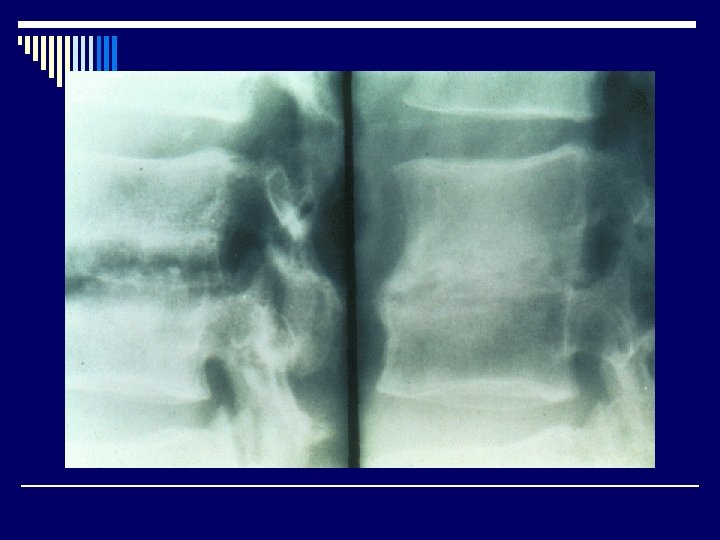

Radiological features o Joint effusion o Erosion o Joint space narrowing o Joint deformity o Osteoporosis o Bony ankylosis

Indication for surgical drainage o Hip and shoulder joint, S-C joint o Vertebral osteomyelitis with cord compression o Thick synovial purulent fluid or loculated o Persistent positive synovial fluid culture o Prosthetic joints o Associated with osteomyelitis o Delayed onset of therapy (>1 week)